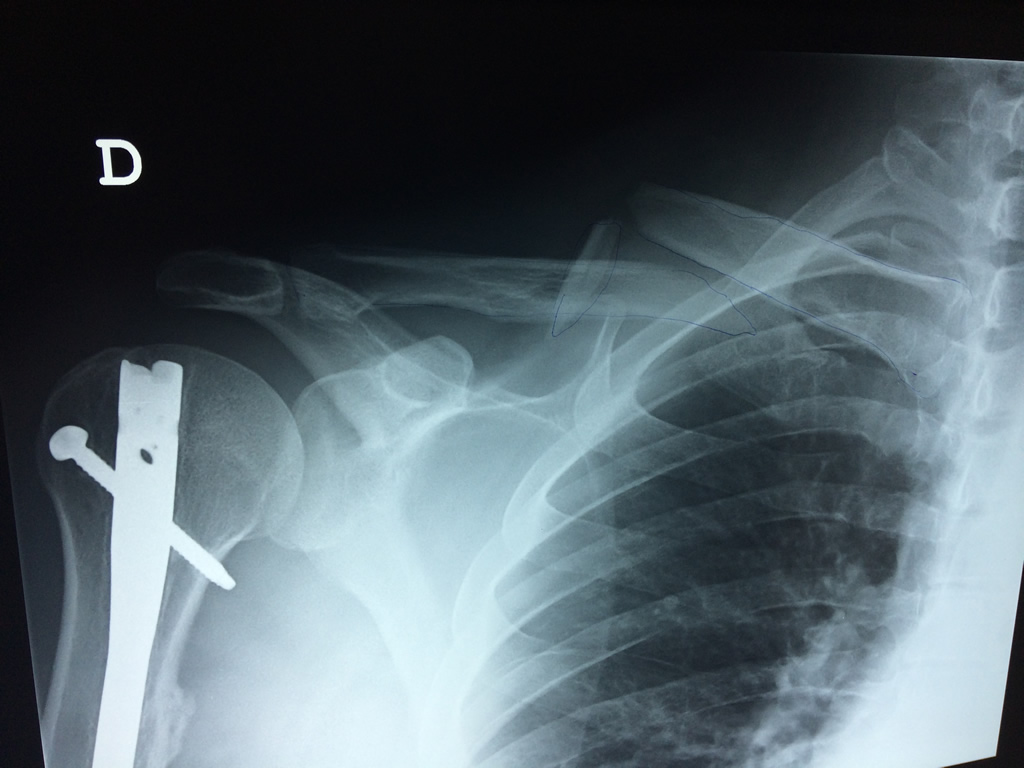

Clavícula

La clavícula es un hueso largo, con forma de "S" itálica, situado en la parte anterosuperior del tórax. Junto con la escápula forman la cintura escapular. Se puede palpar por toda su longitud y se extiende del esternón al acromion de la escápula, siguiendo una dirección oblicua lateral y posterior.